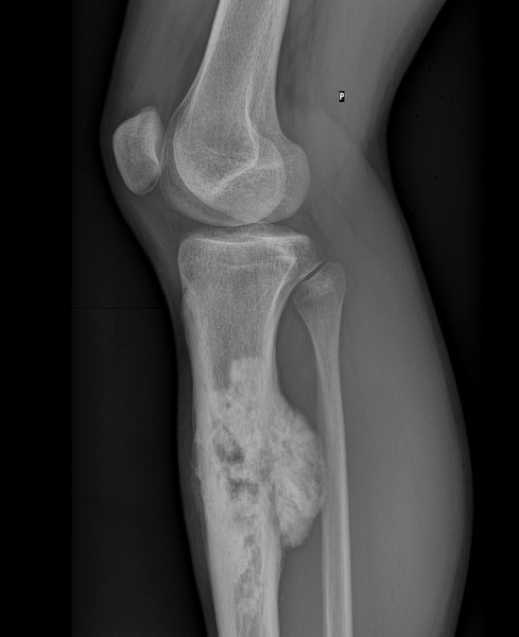

- “Chicken-drumstick appearance” (metaphyseal growth)

- Codman’s triangle: periosteal elevation due to subperiosteal tumour spread

- Sites: knee and shoulder (distal femur/proximal tibia or humerus)

- X-ray: “moth-eaten” lytic lesion with onion-skin periosteal reaction